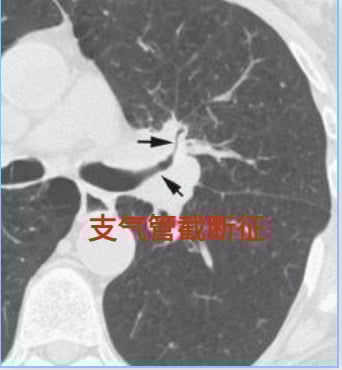

支气管截断征:气道被阻断的迹象

支气管截断征是指支气管因癌肿的侵蚀、破坏和占位,在CT影像上呈现出杯口状、平直或漏斗状的突然中断,远端肺纹理随之缺失。这是肺癌极具辨识度的CT征象之一。然而,需要注意的是,创伤性气管损伤、支气管闭锁、肺隔离症、支气管囊肿、支气管异物、支气管腺瘤等良性病变也可能出现类似表现,因此需要结合临床情况进行仔细鉴别。